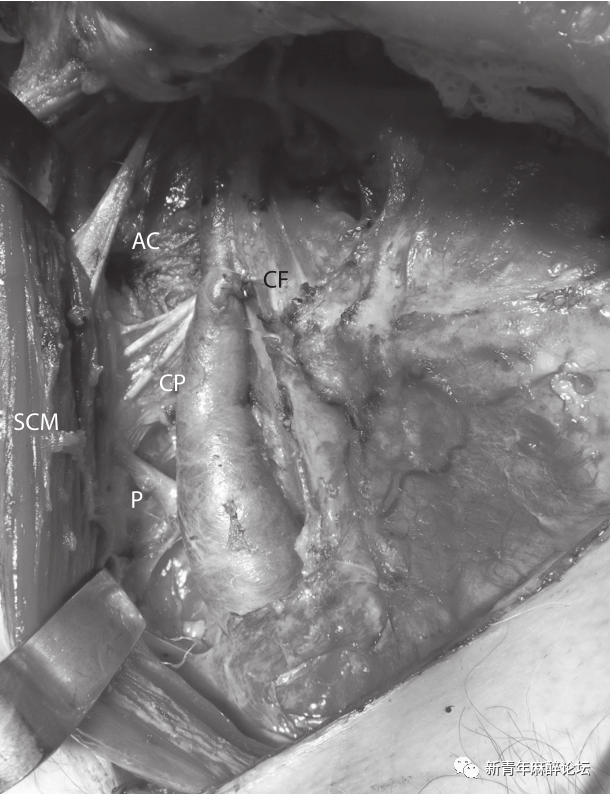

72岁男性,右后颊粘膜/磨牙后区鳞状细胞癌(T1N0M0),作为这种癌症的切除和重建手术的一部分,行预防性择期右颈淋巴结清扫术(1-4级)。在2-4级颈淋巴结清扫术中,可见从胸锁乳突肌(sternocleidomastoid muscle,SCM)内侧向前下方走向的一支后支静脉汇入IJV的下1/3(图1)。

图1:右颈内静脉后支:AC-副神经、CF-面总静脉(已结扎)、CP-颈丛、SCM-胸锁乳突肌、P-后支